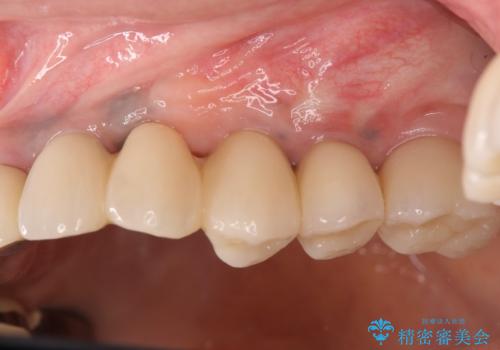

インプラント治療を行ったことでしっかりとした咬合関係を確立することができました。